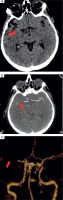

Twelve hours after admission to ICCU, in the presence of medical staff, the patient experienced symptoms of the stroke such as dysarthria, drooping of the corner of the mouth at the left side, and severe weakness of the left upper and lower limbs. The computed tomography (CT), which was performed immediately, showed that a high attenuation of the right middle cerebral artery (RMCA) was present (Figure IA). Angio-CT of cerebral arteries confirmed the occlusion of RMCA at segment M1/M2 about 6.5 mm from the origin of RMCA (Figure IB). The VRT (volume rendering technique) reconstruction of cerebral arteries was performed based on angio-CT (Figure IC).

Figure I

A) Computed tomography without contrast – hyperdense right middle cerebral artery (RMCA). B) Angio-CT – occlusion of RMCA in M1/2 segment. C) VRT (volume rendering technique). Arrows show pathological lesions